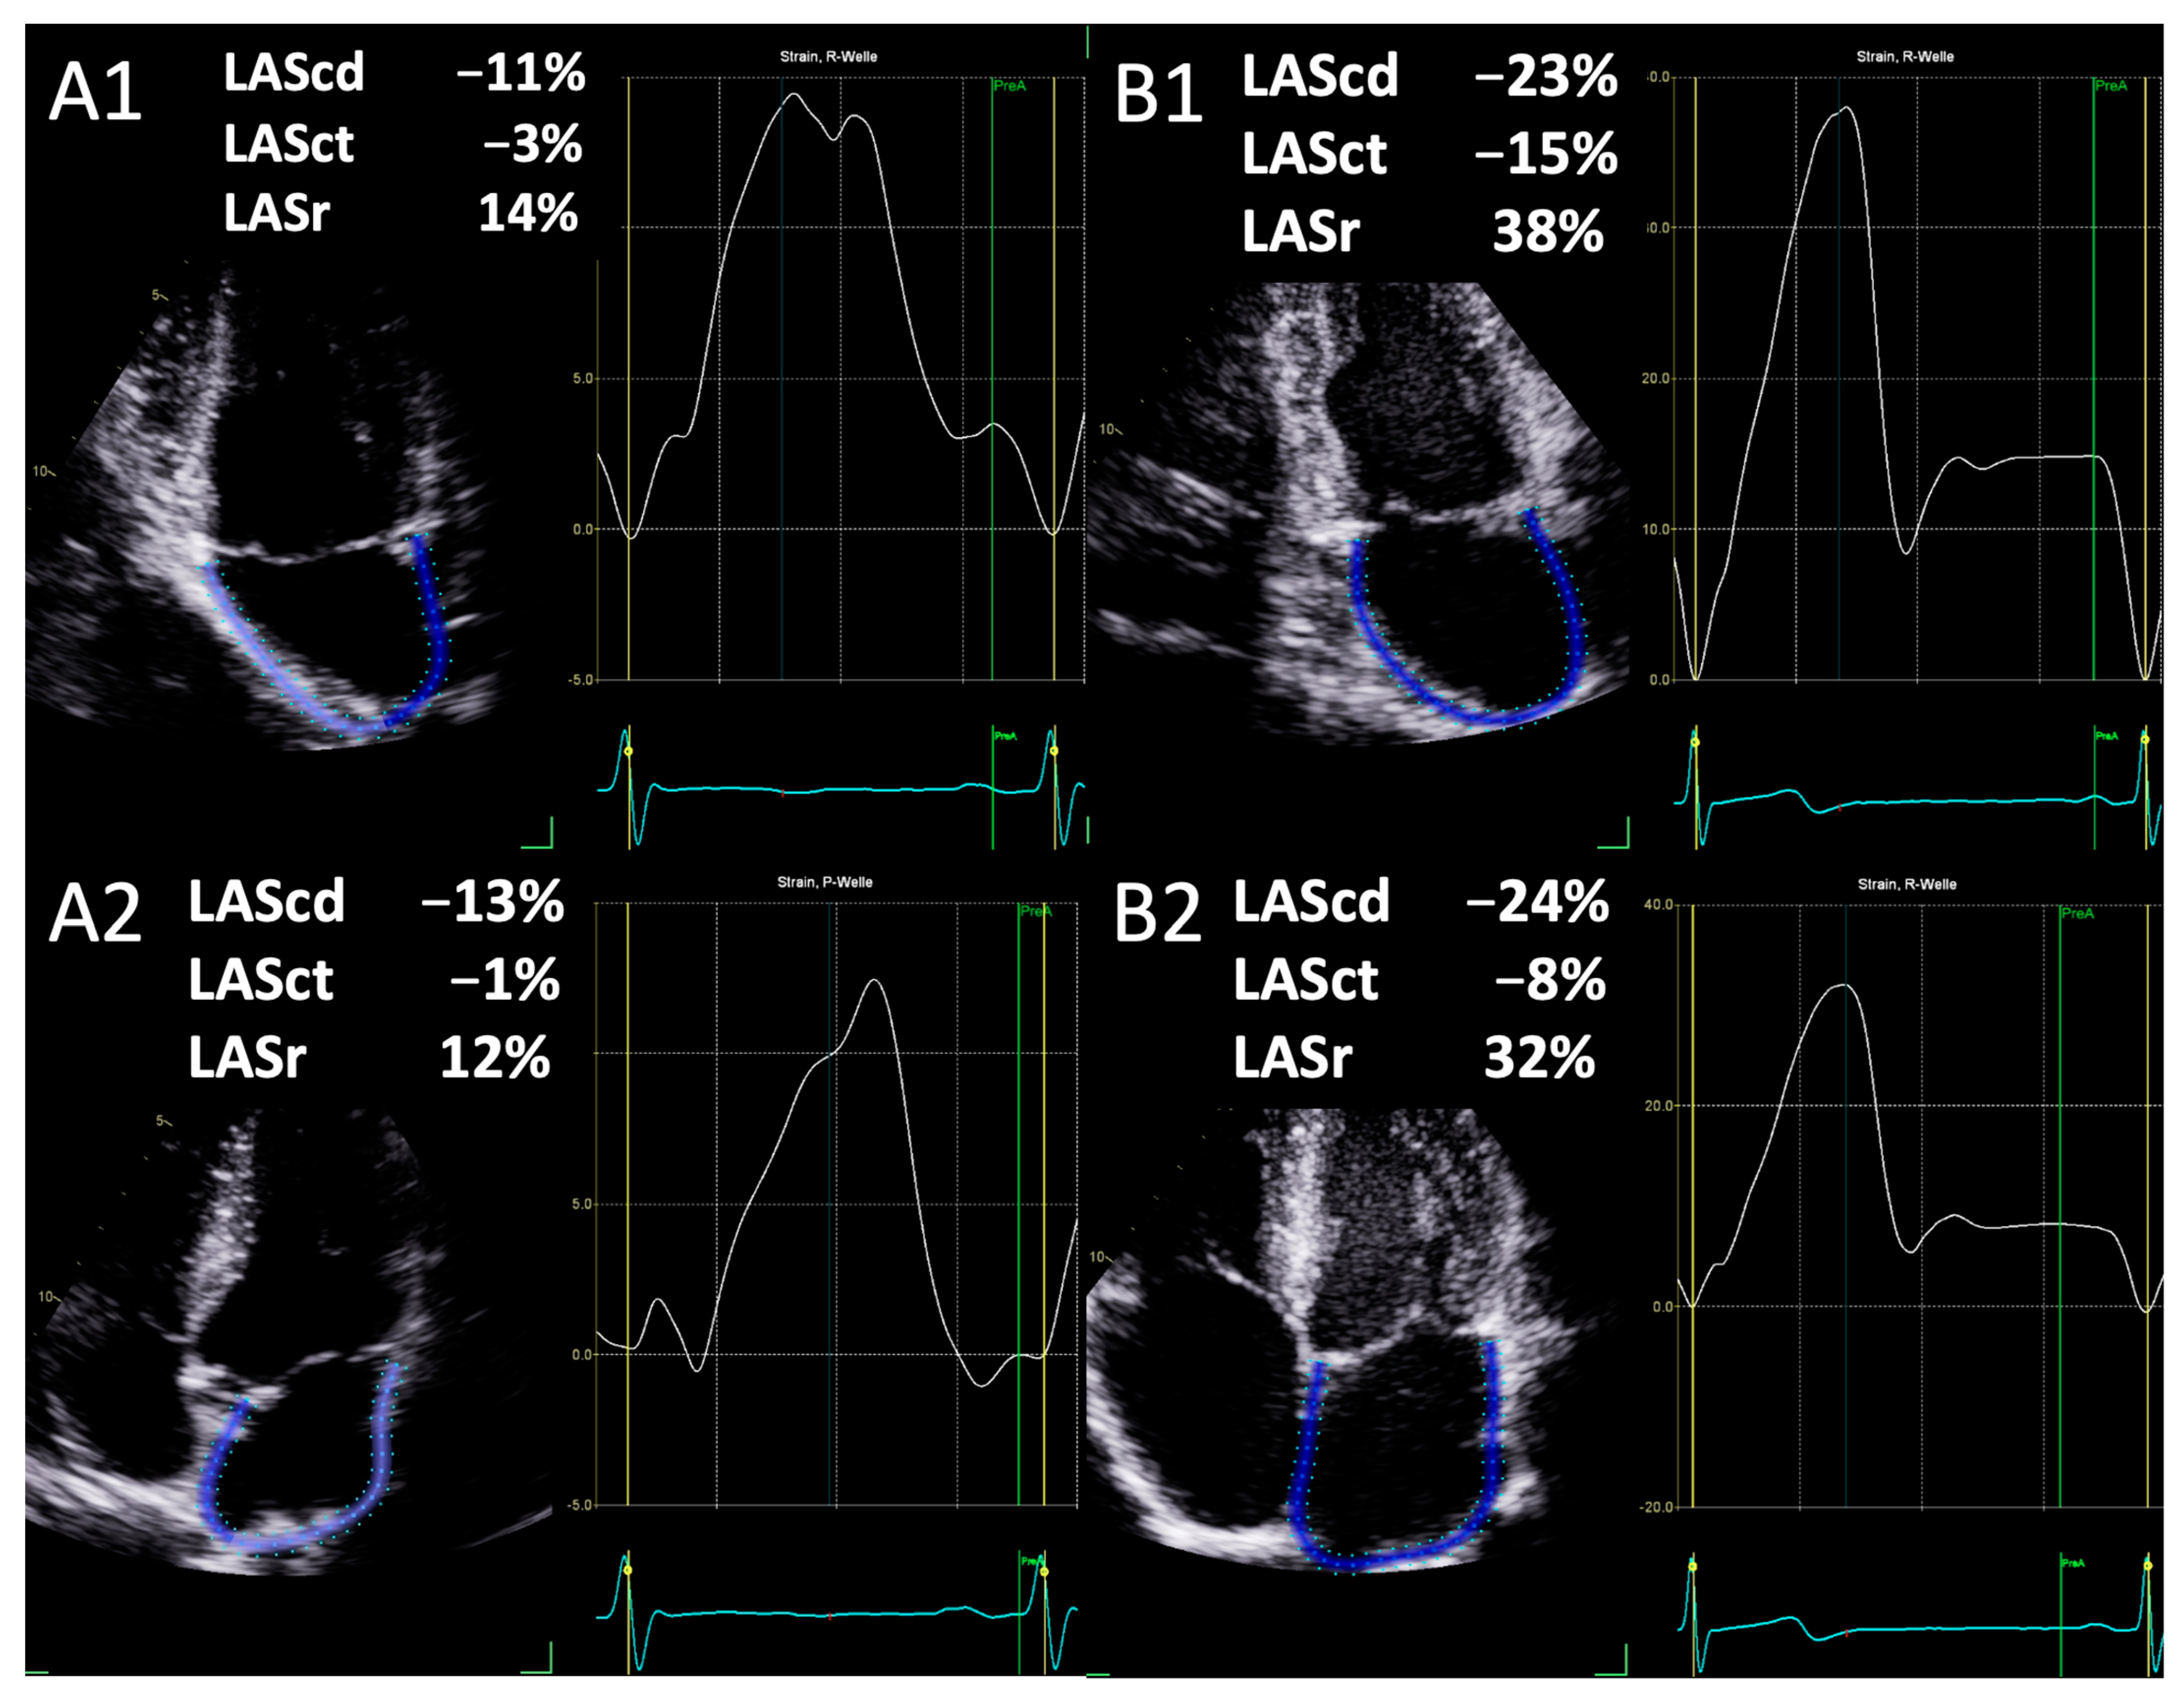

2.2. Parameters of Left Atrial Deformation

| Conduction Strain (%) | −13.9 ± 6.5 | −26.9 ±6.9 | <0.001 |

| Contraction Strain (%) | −4.0 ± 3.3 | −9.0 ± 4.1 | <0.001 |

| Reservoir Strain (%) | 17.9 ± 7.5 | 34.4 ± 13.4 | <0.001 |

| Conduction Strain (%) | −14.0 ± 7.8 | −27.7 ± 9.0 | <0.001 |

| Contraction Strain (%) | −5.4 ± 4.9 | −12.2 ± 9.9 | <0.001 |

| Reservoir Strain (%) | 19.6 ± 10.4 | 41.6 ± 9.7 | <0.001 |

| Conduction Strain (%) | −14.0 ± 5.9 | −27.4 ± 7.1 | <0.001 |

| Contraction Strain (%) | −4.6 ± 3.5 | −11.3 ± 4.1 | <0.001 |

| Reservoir Strain (%) | 18.7 ± 7.6 | 38.7 ± 8.0 | <0.001 |